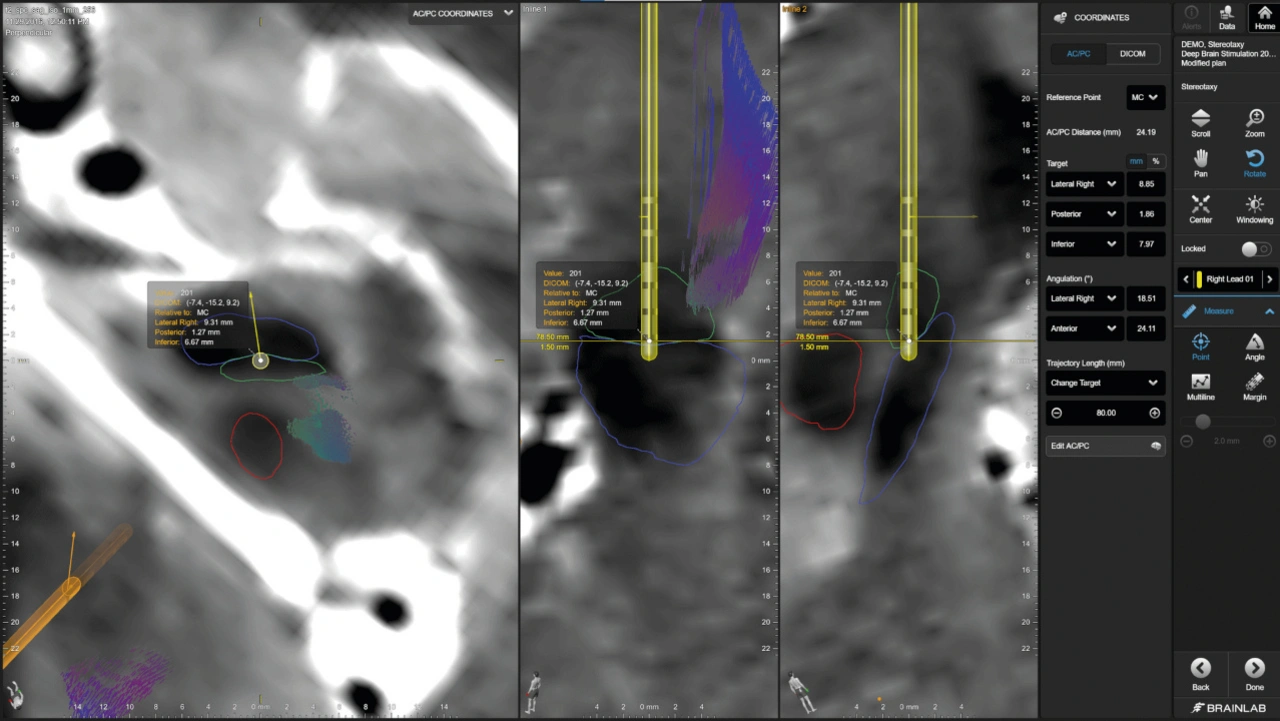

Bild 2. Dank der 3D-Visualisierung der Elektrodengeometrie, der automatisierten Elektrodenerkennung und der direktionalen Schätzung der Elektrodenausrichtung mittels Boston Scientific Vercise Cartesi-Richtelektroden ist es möglich, die genaue Platzierung von DBS-Elektroden zu ermitteln, so das Ziel exakt anzusteuern und eine genaue Patientenprogrammierung sicherzustellen.

Nachdem ChirurgInnen den Zielbereich im Gehirn als Startpunkt definiert haben, erfolgt die Trajektorienplanung: Mithilfe von 2D- und 3D-Visualisierung sowie flexibler 3D-Elektrodenmodellierung simuliert sie die geplante Trajektorie, um die Sicherheit des Eingriffs zu gewährleisten und mögliche Komplikationen zu minimieren.

Intraoperative Genauigkeit in Echtzeit

Nach Abschluss der präoperativen Planung beginnt der intraoperative Teil des DBS-Verfahrens – ein kritischer Moment, in dem die zuvor virtuell geplante Strategie in die klinische Realität überführt wird. Mobile intraoperative Bildgebungssysteme unterstützen beispielsweise die stereotaktische Rahmenlokalisierung. Spezialisierte Softwarelösungen fusionieren Bilddaten in Echtzeit mit den präoperativ geplanten Modellen. Anhand von entweder intraoperativ aufgenommenen 3D- oder 2D-Aufnahmen können die implantierten Elektroden automatisch visualisiert und als 3D-Elektrodenformen modelliert werden, sodass medizinische Fachkräfte ihre akkurate Positionierung noch während der OP überprüfen können.